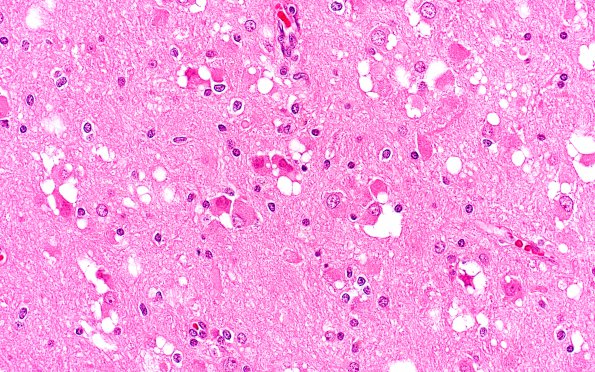

Multinodular Vacuolating Neuronal Tumor

2B6 MVNT (Case 2) B2 H&E 40X 1

2B6-9 Various magnifications of vacuolated neurons. (H&E)